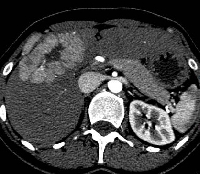

Πρόκειται για γυναίκα ασθενή 32 ετών, η οποία υποβλήθηκε σε αξονική τομογραφία για άτυπα γαστρεντερικά συμπτώματα και άνοδο των ηπατικών ενζύμων. Διαπιστώθηκε συμπαγής μάζα του ήπατος, η οποία εντοπίζονταν τόσο στο δεξιό (τμήματα 5 και 8) όσο και στον αριστερό (τμήμα 4) λοβό. Η ηπατική ογκομέτρηση ανέδειξε ότι τα τμήματα 1, 2 και 3 αποτελούσαν το 30% του συνολικού όγκου του οργάνου (εικόνες 1, 2). Υποβλήθηκε σε δεξιά εκτεταμμένη ηπατεκτομή (εικόνα 3). Στο παρασκεύασμα φαίνεται η μάζα. To μέγεθός της ανέρχεται σε 8 εκατοστά (εικόνα 4). Σε οβελιαία τομή, διακρίνεται η χαρακτηριστική κεντρική ουλή της εστιακής οζώδους υπερπλασίας (εικόνα 5). Ο σχετικός όγκος του υπολοιπόμενου ήπατος ανήλθε στο 64%, ένα μήνα μετά την ηπατεκτομή (εικόνα 6). Η ασθενής είναι ελεύθερη συμπτωμάτων.